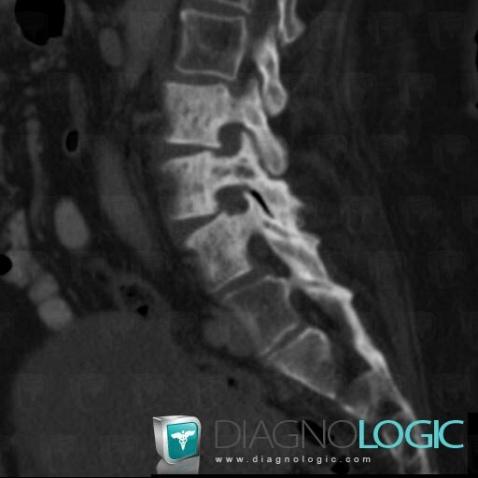

Metastasis, Vertebral body / Disk, CT

Here is the specific information in the key image above:

- Diagnosis Metastasis, Location(s) Vertebral body / Disk, with gamuts Pedicle sclerosis